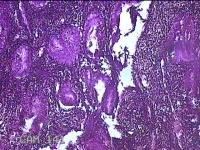

宫腔赘生物

性别

女

年龄

50岁

临床诊断

异常子宫出血 子宫腔赘生物待查 子宫肌瘤 疤痕子宫

一般病史

不规则流血25天,增多7天。

标本名称

大体所见

灰白粉红色肿物1x0.8x0.2cm两个,表面光滑。